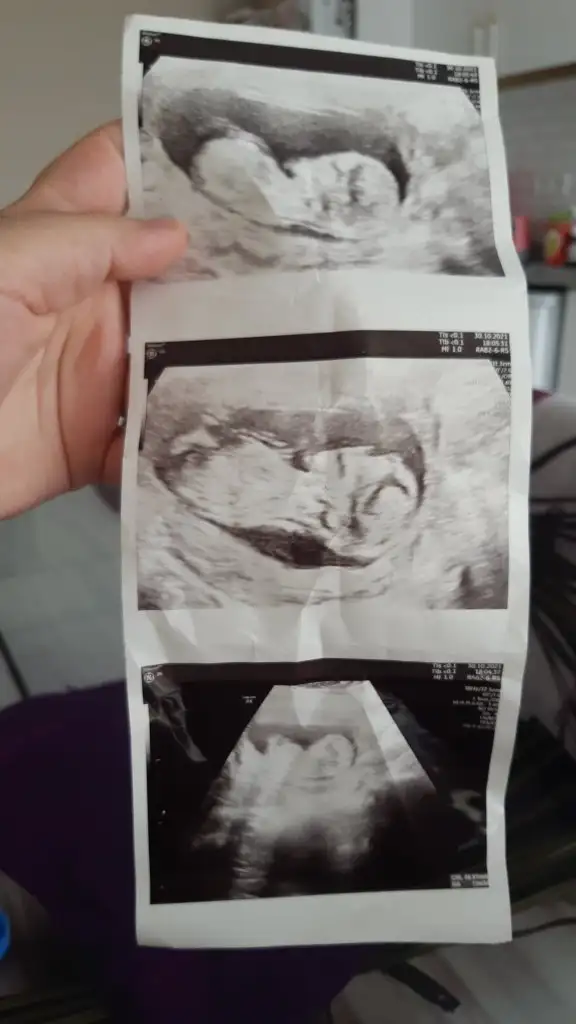

Merhabalar herkes sizi öneriyor bana da bir tanminde bulunur musunuz tam 14 haftalık ama kordon girdiği için emin olmamakla beraber erkek dendi içimden hep kız geçiyor rüya test vs ile cuma kesinleşecek ama sizden tahmin etmenizi istiyorum yardımcı olur musunuz 🌼

• 1637176680255726725434354118476.webp

1637176680255726725434354118476.webp

32,7 KB · Görüntüleme: 73

• 16371767028034893220570748574732.webp

16371767028034893220570748574732.webp

21,9 KB · Görüntüleme: 64

• 16371767370174977016383944932975.webp

16371767370174977016383944932975.webp

21,1 KB · Görüntüleme: 65

Bu haftalarda nub olmaz cnm 11 12 13 haftalar olmalı şekli kıza benzetim

Doktor %70 kiz gibi ama daha erken onumuzdeki ay net belli olur dedi. Fakat prof dr oldugu icin yanilacagini sanmiyorum. Senin dr baya namini duydum sitede. Sen de emin olamamissin o zaman kız mi geliyor acaba 😊

Ayy Dr yanılmış 🙈 sağlıkla gelsin oğlusun 💙